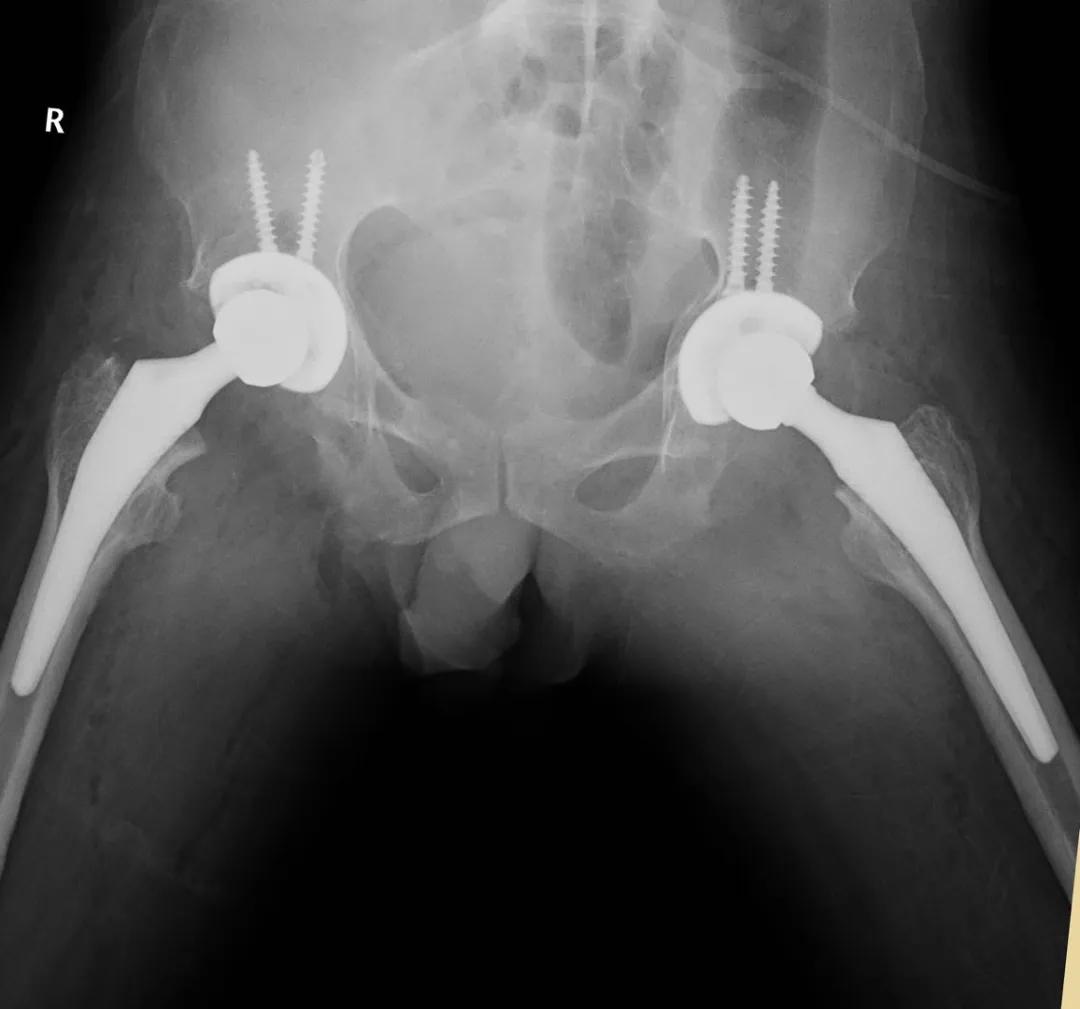

经过充分准备,2019年8月7日在全身麻醉下实施了双侧人工全髋关节置换术。

术后影像学资料

术后经过康复,他的双髋关节功能逐渐开始恢复:

双髋关节被动屈伸0°-80°,右侧外展15°,左侧外展25°,肌肉僵硬的情况也得到了很明显的改善。